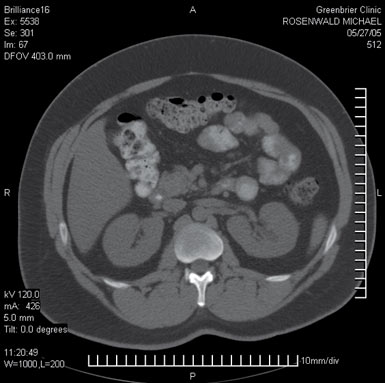

I have no time for fun and games, though. I’ve come for a workup at Greenbrier’s world-renowned health clinic, which caters to executives whose corporations have a vested interest in preventing them from suddenly keeling over. Greenbrier has, for instance, a Philips Brilliance CT 16. It is one of the fastest CT devices in the world, capable of scanning the entire body in 30 seconds as well as snapping images of the heart between beats, a method that can detect the presence of tiny bits of plaque that will eventually cause blockages.

Between tests, I sip on a quart of toxic-tasting contrast agent to light up my bowels on a computer screen during my full-body CT scan (which, I found out, will dose me with radiation equivalent to taking 100 mammograms back to back).

I ask Graves about the controversy over CT scans, and he says he can see both sides of the debate. He tells me about a healthy patient who had a history of normal stress tests and EKGs-not an obvious candidate for any kind of scan. But when the machine scanned his heart, snapping pictures as it contracted, Graves could see that the patient’s arteries were dangerously calcified. The man could have dropped dead, but instead he got an angioplasty. I am convinced.

And then he got to my tests. My CT scans showed an irregular left kidney. Might be a good idea to follow up with a urologist, Graves advised, and instantly I thought of what Mehmet Oz said about discovering things that looked like problems but were not. There was absolutely nothing clogging my arteries. No tumors had formed in my body. (Of course, these scans looked for existing tumors, not for the cells that could cause them to form.) Then Graves said something I will never forget.